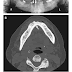

Mujer de 65 años con úlcera crónica de la mandíbula. Osteonecrosis asociada a bifosfonatos.

Presentación del caso: Una mujer de 65 años fue vista en una clínica quirúrgica debido a úlcer mandibular que no cicatrizaba. Tres años...